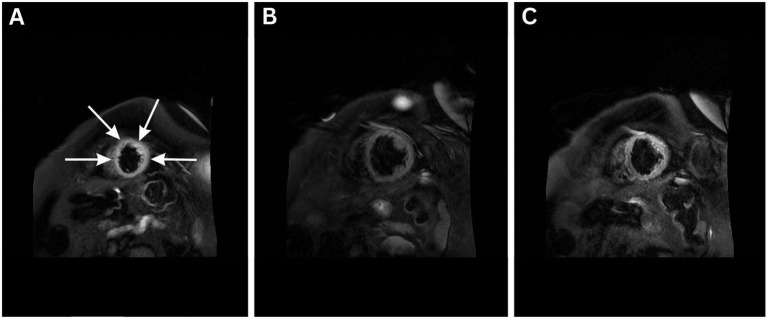

Case description: A 77-year-old woman with hypertension, diabetes, and a permanent pacemaker presented with acute dyspnea and subsequently experienced cardiac arrest. Post-resuscitation, she was found to have anterolateral ST elevations, apicomedial akinesis, and severely reduced LVEF (22%), consistent with Takotsubo cardiomyopathy. Despite appropriate antimicrobial therapy and supportive care, she developed worsening fever, marked hemodynamic instability, hyperlactatemia (14 mmol/L), atrial fibrillation, raising suspicion for a systemic hyperinflammatory response. Hemoadsorption therapy with CytoSorb was initiated in a stand-alone configuration, alongside corticosteroids and targeted temperature management. The patient showed marked improvement in hemodynamics, organ function, and urine output within 48 h, without the need for renal replacement therapy. She was later extubated and discharged home.